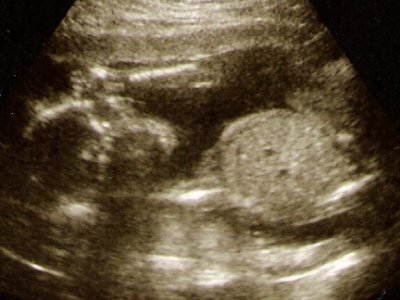

Csütörtökön voltunk a Péterfyben genetikai Uh-on, ahol észrevették, hogy van két plexus chorioideus cystája Marcinak. Ez az agy egy részén lévő felritkulás, ami nem igazi cysta, mert nincs sejtfala.

Ha más eltérés is van, akkor nagy a valószínűsége valami kromoszómarendellenességnek.

Így pénteken elmentünk az Istenhegyi klinikára is. Bátorfi doktor vizsgált meg, aki nagyon alapos és kedves volt.

A kombinált teszt és az AFP eredménye, na meg az általa végzett nagyon alapos UH alapján azt mondta, hogy ez nagy valószínűséggel csak egy olyan cysta ami pár héten belül felszívódik, és semmi nyoma nem lesz.

Én hiszek neki. Úgy érzem Marci teljesen egészséges, és így is fog megszületni.

És íme két kép róla:

Kép Kép